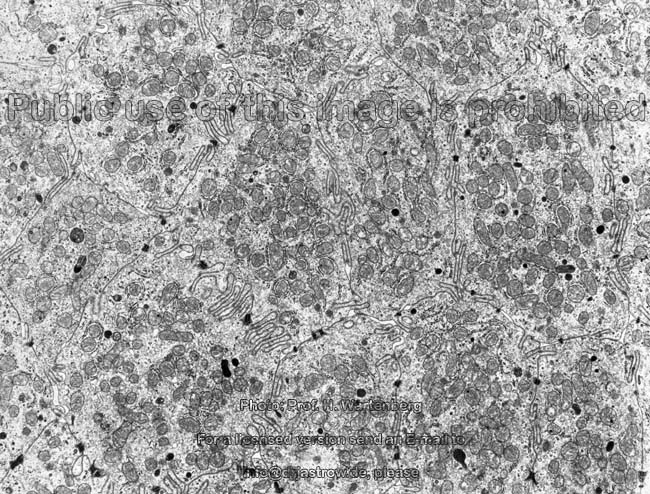

Miniaturbildübersicht Zwölffingerdarm (Duodenum):

Die Oberfläche der Schleimhaut zeigt mit bloßem Auge gerade noch erkennbare sehr feine ca. 0,5 - 1,5 mm finger- bis blattförmige zum Lumen hin gerichtete Erhebungen, die sie samtartig erscheinen lassen. Diese Erhebungen werden als Darmzotten (Terminologia histologica: Villi intestinales, englisch: intestinal villi) bezeichnet und sorgen für eine ca. 6- fache Oberflächenvergrößerung. Dazwischen sind schlauchförmige in die Tiefe ziehende feine Kanälchen mit nur ca. 0,1 mm Durchmesser zu finden, die Lieberkühnsche Krypten (Terminologia histologica: Cryptae intestinales, Glandulae intestinales; englisch: intestinal villi, intestinal glands) heißen. Ganz am Grund einiger, aber bei weitem nicht aller, Krypten münden die Ausführungsgänge der nur im Duodenum vorkommenden Brunnerschen Drüsen, die in der Submukosa liegen (siehe unten). Sowohl auf den Zotten als auch in den Kypten findet sich

1. (einschichtig hochprismatisches Epithel (Terminologia histologica: Epithelium simplex columnare, englisch: simple colmnar epithelium). Hier finden sich ganz überwiegend die Saumzellen, die auch als Resorptionszellen oder Enterozyten (Terminologia histologica: Enterocyti, englisch: enterocytes) bezeichnet werden. Auf ihrer zum Lumen hin gerichteten Oberfläche bilden sie einen Bürstensaum aus (Terminologia histologica: Limbus microvillosus, Limbus penicillatus, Limbus striatus; englisch: microvillous border, brush border, striated border), der aus unzähligen exakt parallel zueinander stehenden am Terminalgespinst in der Zelle verankerten 1,2 -1,5 µm langen, 0,08 µm durchmessenden Mikrovilli besteht und für eine ca. 600 - fache Oberflächenvergrößerung auf ca. 200 m² sorgt, die für die Resorption von Nährstoffen essentiell ist. Auf der Oberfläche der Mikrovilli findet sich eine stark ausgeprägte Glykokalyx, in der Zellmembran der Mikrovilli sind sehr viele Transportproteine und Ekto- (außerhalb der Zelle wirkende) Enzyme  lokalisiert, die für die Verdauung bzw. den transmembranösen Stofftransport im Zuge der Resorption der Nährstoffe wichtig sind. Dabei handelt es sich z.B. um Oligosaccharidasen + Disaccharidasen, die Nahrungszucker in Ihre Bestandteile, vor allem Glucose, Galaktose und Fruktose zerlegen. Während

Fruktose passiv resorbiert wird (mit Wasser über die Poren des Zwischenzellraums), gibt es energieverbrauchende (aktive) Transportproteine für Glucose und Galaktose im gekoppelten Transport mit Na+. Bis zu 60 % der Nahrungsproteine und ein beträchtlicher Teil der Nahrungsfette werden schon im Duodenum aufgenommen. Deshalb lassen sich auch zwischen den Mikrovilli viele Endozytosevorgänge an der Zelloberfläche erkennen. Neben den Enterozyten liegen nach analwärts zunehmend häufigere Becherzellen (Terminologia histologica: Exocrinocyti caliciformes, englisch: goblet cells), die mit ihrer Ausscheidung vom Schleimstoffen (Muzinen, insbesondere MUC2) zur Bildung einer schützenden Schleimschicht beitragen, welche die Gleitfähigkeit des Speisebreis (Chymus) erhöht. Nur sehr selten, und auch nur oberhalb der Spitze tiefer in der Lamina propria gelegener Lymphfollikel (daher die Bezeichnung Domzellen), lassen sich die ebenfalls im Epithel gelegenen M-Zellen entdecken (Mikroplika-Zellen, Domzellen, Terminologia histologica: Epitheliocyti microplicati; englisch: microfold cells, M-cells, dome epithelial cells). Diese mit dünnen, flachen Erhebungen (Mikroplicae) an der Oberfläche ausgestatteten Epithelzellen gehören zum Darm-assoziierten lymphatischen Gewebe und schleusen per Transzytose Antigene durch die Epithelbarriere zu den Lymphfollikeln, was für Immunisierungsvorgänge, z.B. bei Schluckimpfungen wesentlich ist. Enterozyten und Becherzellen leben nur ca. 5 Tage und gehen aus Stammzellen hervor, die sich in der unteren Hälfte der Krypten befinden. Die Zellen werden nach oben gedrängt und wandern bis zur Zottenspitze wo sie nach programmiertem Zelltod (Apoptose) absterben und ins Lumen abgegeben werden. Sobald die Zellen den oberen Bereich der Krypte erreicht haben, sind sie ausgereift und voll funktionsfähig. Im Gegensatz dazu verbleiben die am Kryptengrund lokalisierten deutlich längerlebigen enteroendokrinen Zellen dort. Die meist kleinen Sekretvesikel der enteroendokrinen Zellen liegen unterhalb des Zellkerns, weil sie ja nach basal sezerniert, d.h. per Exozytose abgegeben werden. Enteroendokrine Zellen bilden Hormone, die nach basal, d.h. in die darunter gelegene Lamina propria und letztlich deren Kapillaren, Venolen und Lymphgefäße gelangen. Eine Zusammenstellung enteroendokriner Zellen findet sich hier.